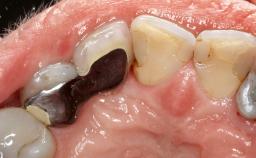

Mauricio Araujo and Flauvia Matarazzo present this straightforward clinical case, demonstrating the potential effect of implant placement depth on the resolution of peri-implant treatment. A 42-year-old systemically healthy female patient, a non-smoker with no history of periodontitis, was treated at the Dental Clinic at the State University of Maringá, Brazil between 2008 and 2009, when she received five implants restored with single crowns at sites 14, 26, 27, 36, and 46. After delivery of the implant-supported prosthetic restorations, the patient was enrolled in the supportive peri-implant therapy (SPiT) maintenance program at the same university.